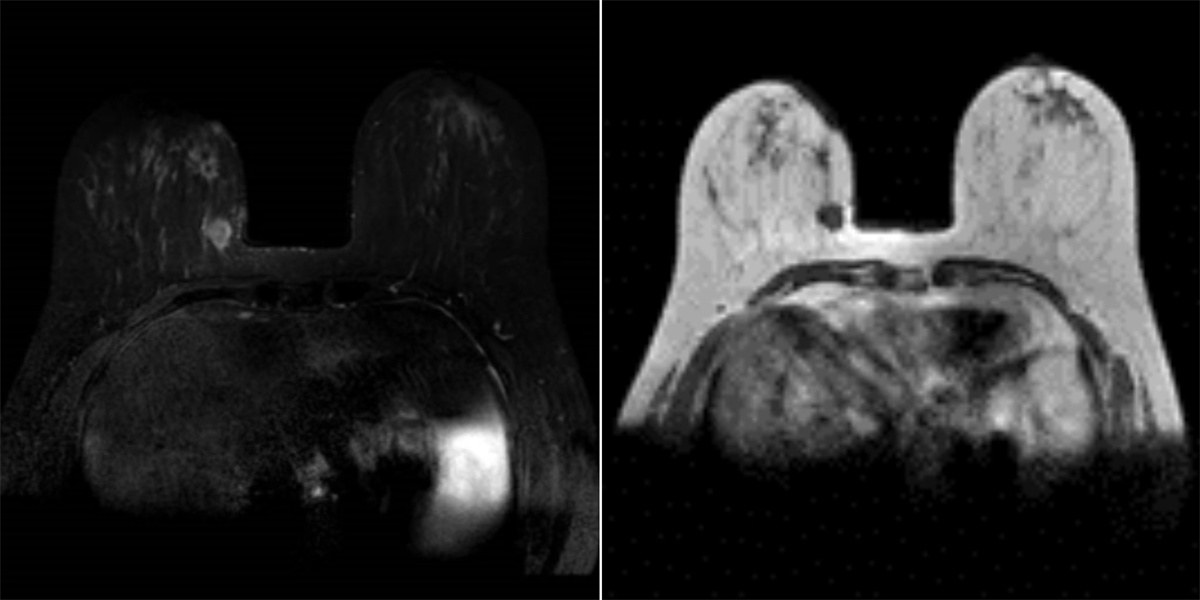

67岁的患者郭女士,因“右乳肿物”入院。经查双乳房表面皮肤无红肿破溃,无卫星结节,右侧乳房有2个肿物分别与不同象限,2x2cm,两个乳腺肿物均是恶性肿瘤。根据CACA-CBCS(2022版)指南、以及考虑患者本身年龄及病情,不适合保留乳房手术。但郭女士对切口的长度及位置有强烈的要求及意愿。经乳腺外一科团队会诊,并与家属充分沟通后,最终选择此术式。

52岁的患者佟女士,因“左乳肿物”入院。经查双乳房表面皮肤无红肿破溃,无卫星结节,左侧乳房肿物2x2cm。腋下淋巴结肿大融合2x2cm,给予系统治疗后。此次入院检查适合手术。根据CACA-CBCS(2022版)指南、以及考虑患者本身年龄及病情,不适合保留乳房手术。

崔舜瑀教授带领团队在术前进行了充分的病情分析、术前切口的标记与测量,依照两位女士的意愿,为她们量身定制了个性化的手术方式和预案准备。术中,团队使用自制的“乳腺单孔腔内镜戳卡”进行操作,1例采用“逐层法”切除全部腺体并完整保留乳头乳晕。1例采用“逐层法”切除全部腺体及乳头乳晕,手术过程十分顺利。目前患者切口愈合良好,术区无任何异常,无不良反应及并发症,此术式在避免术后放疗的同时,兼顾健康和美观,且“无痕”,患者及家属表示非常满意,并顺利出院。